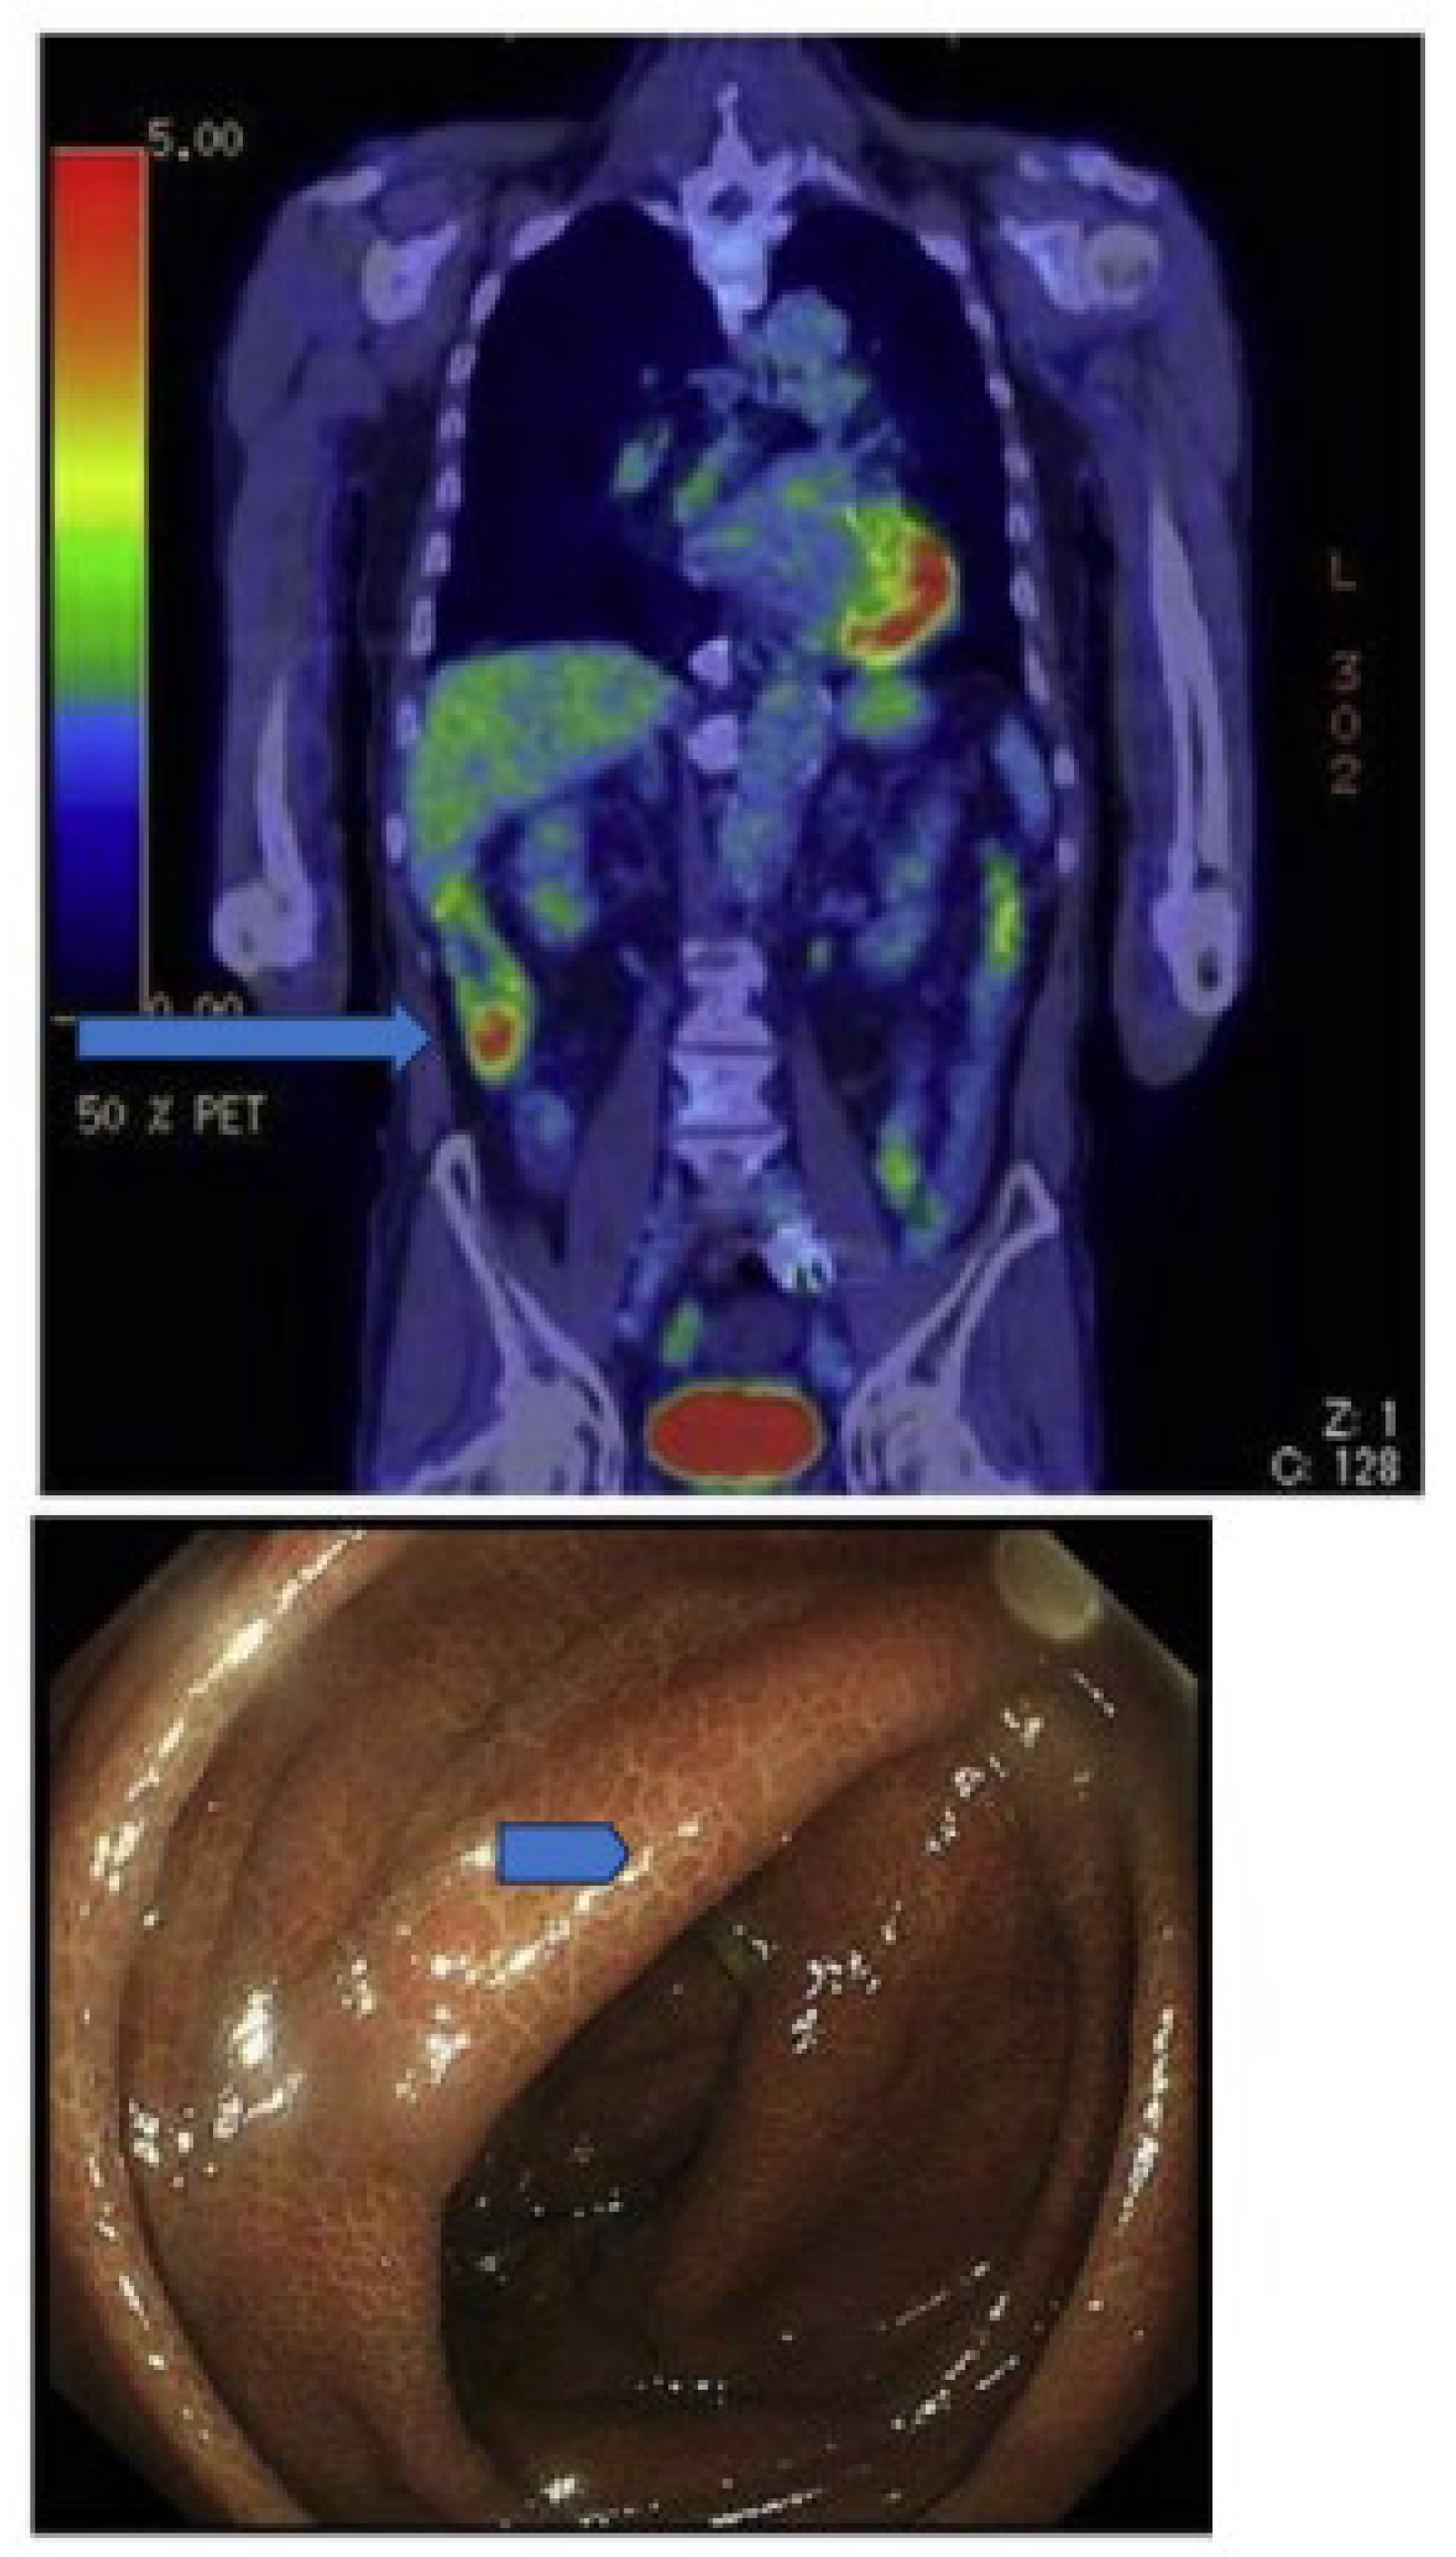

C11-metformin (9.5 microSv/MBq = ca.1.1 micrograms), first injected intravenously, allowed the study of its biodistribution in humans by the PET scan technique [133]. Most of the activity was found in the liver, the kidneys, and the urinary bladder. Most of the absorbed compound was cleared from the blood 20 min after injection. Dosimetry calculations were performed for the stomach-, small intestine-, liver-, kidney-, and bladder contents. It was demonstrated that hepatic metformin uptake is very rapid and fully reversible, but the accumulation of the activity was higher than after intravenous administration since, although slower, the tracer delivery came from the portal blood through the liver first. Two hours after the oral ingestion of the tracer, the bulk of the radioactivity was still found in the intestine (Figure 1 lower panel), and no further observation of the fate of the radioactive metformin was possible.

Figure 1.

Scans of C11-metformin administered to humans intravenously and orally (upper (A) and lower (B) panel, respectively) taken at different times after administration. Gormensen LC et al. ([133], with permission).

The kidney-to-blood activity ratio was identical independently of the administration route of the radioactive metformin. Some discrete uptakes of the tracer was found in the salivary glands, and discrete uptake was found also in the intestine. No activity was found in the gallbladder. Significant amounts of the tracer passed to the small intestine 10 min after ingestion.